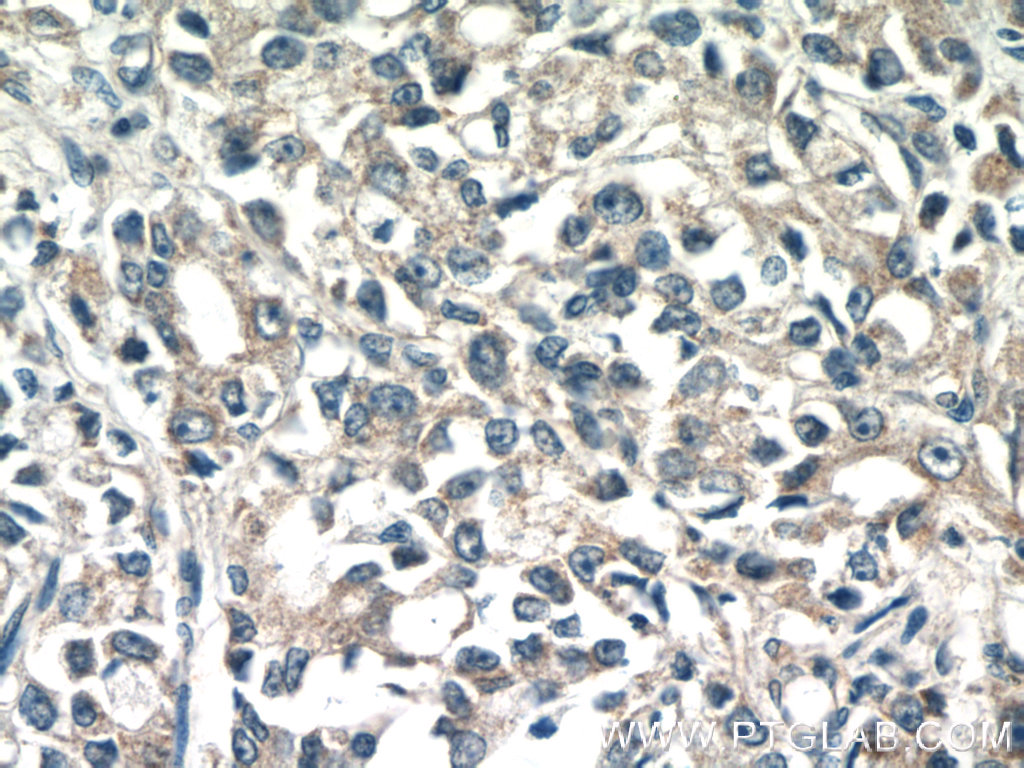

TMEM71 抗体

产品名称: TMEM71 抗体

英文名称: TMEM71 Antibody

产品编号: XY16722-1-

使用范围: WB,ELISA,IHC-P,IHC-F,IF